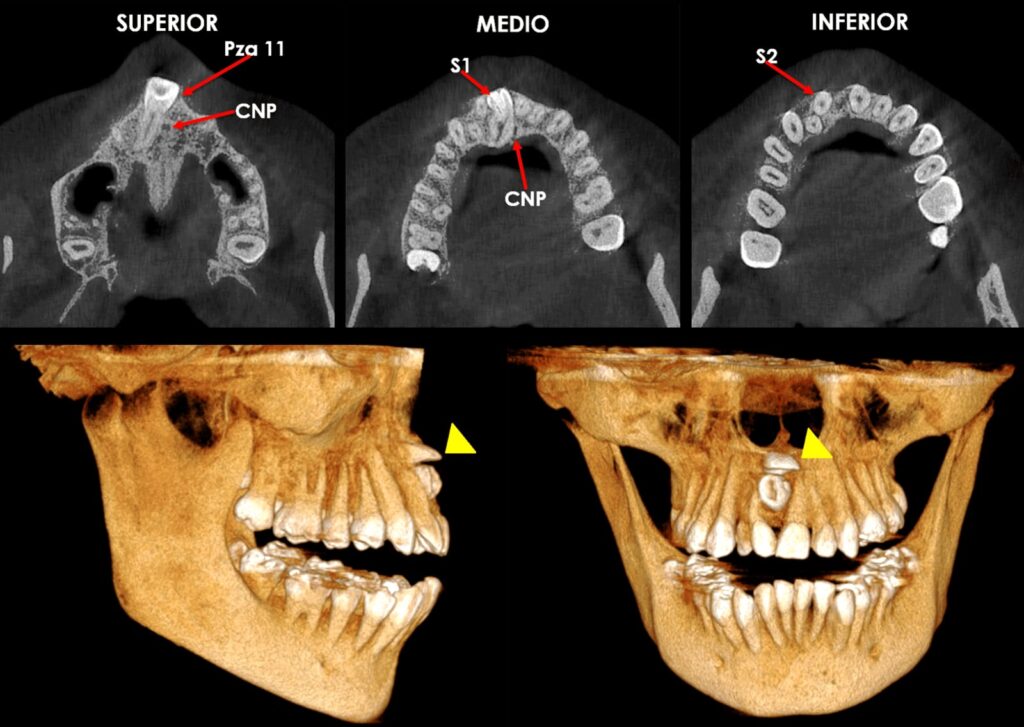

TOMOGRAFÍA AXIAL COMPUTARIZADA

Medio de diagnóstico tridimensional que se realiza en convenio con ………….. ………..para ayudar a mirar la cantidad y calidad del hueso podemos ver estructuras anatómicas y patológicas presentes en el hueso